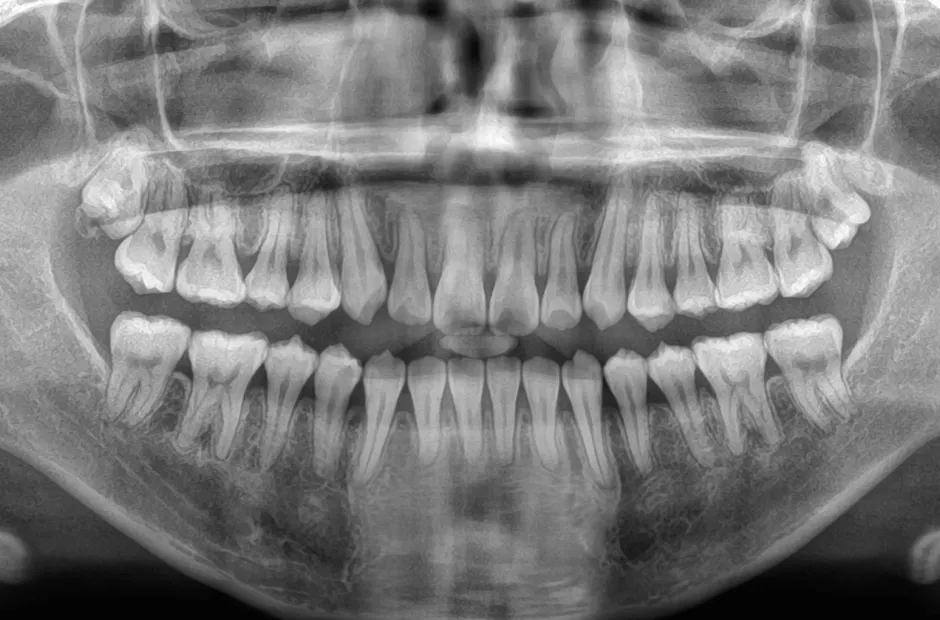

叢生

| 診断名・主訴 | 叢生 |

|---|---|

| 年齢・性別 | 43歳・女性 |

| 治療期間・回数 | 2年7か月 27回 |

| 治療に用いた主な装置 | 舌側矯正 |

| 抜歯部位 | 両顎4,4 |

| 治療費 | 100万円(税抜) |

| リスク・副作用 | 装置による違和感・疼痛・歯肉退縮・歯根吸収・虫歯のリスクなど |